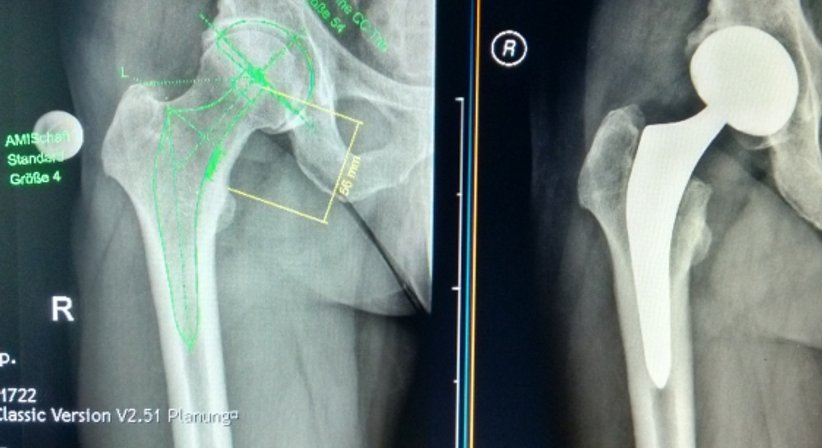

Operative Behandlung der Coxarthrose

Konservative Behandlungen können den weiteren Krankheitsverlauf zwar deutlich verzögern, jedoch nicht komplett aufhalten bzw. den Knorpelabbau nicht wieder rückgängig machen. Schreiten die Beschwerden trotz konservativer Therapie voran, ist ein künstlicher Ersatz vom Gelenk die einzige Möglichkeit, um den vollen Funktionsverlust der Hüfte zu verhindern.

Hierfür stehen unterschiedliche Prothesen und Operationsmethoden zur Wahl. Besonders vorteilhaft ist die Operation nach der AMIS-Methode, einer minimal-invasiven Operation bei welcher der Zugang zu Hüftgelenk von vorne erfolgt. Der große Vorteil dieser Technik gegenüber anderen Operationen besteht darin, dass kein Durchtrennen der Muskeln notwendig ist - diese werden während des Eingriffes zur Seite gehalten. Auf diese Weise entsteht keine Muskelnarbe, was mit einer schnelleren Heilung einhergeht. Weitere Vorteile der AMIS-Methode im Vergleich zu anderen Operationen sind:

- Minimierter Blutverlust

- Aufstehen bereits einen Tag nach der Operation möglich

- Aufenthaltsdauer im Spital von etwa 4 bis 5 Tagen

- Schnellere selbstständige Beweglichkeit

- Kürzere Tragedauer von Krücken

- Kürzere allgemeine Rehabilitationszeit

- Aufnehmen der Arbeit, alltägliche Erledigungen, Sport etc. sind schneller wieder möglich

Der genaue Operationsablauf und der richtige Zeitpunkt für die Operation werden vorab ausführlich in meiner Ordination besprochen und ebenso wie der Nachbehandlungsplan gemeinsam festgelegt.

Meine Operationen am Hüftgelenk führe ich im KH der Barmherzigen Brüder in Eisenstadt durch. Die Wartezeit auf einen künstlichen Hüftgelenksersatz beträgt derzeit etwa 5-6 Monate.